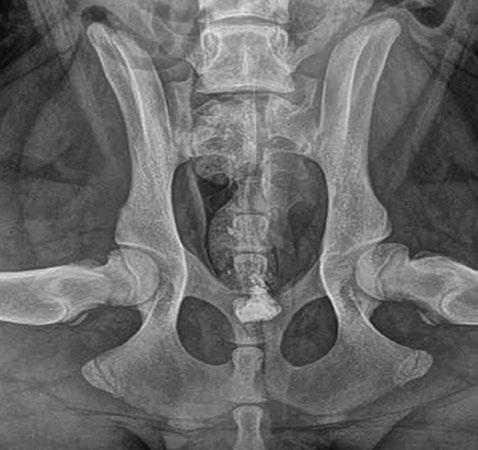

Issuu converts static files into: digital portfolios, online yearbooks, online catalogs, digital photo albums and more. Sign up and create your flipbook.